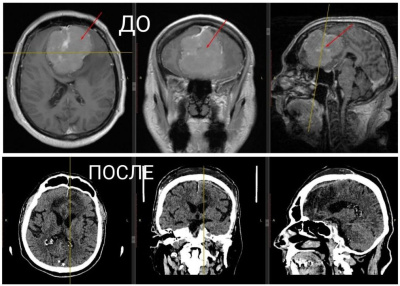

Он уже долгое время мучился от сильных головных болей, головокружения, ухудшения зрения и памяти, но к врачам не обращался.